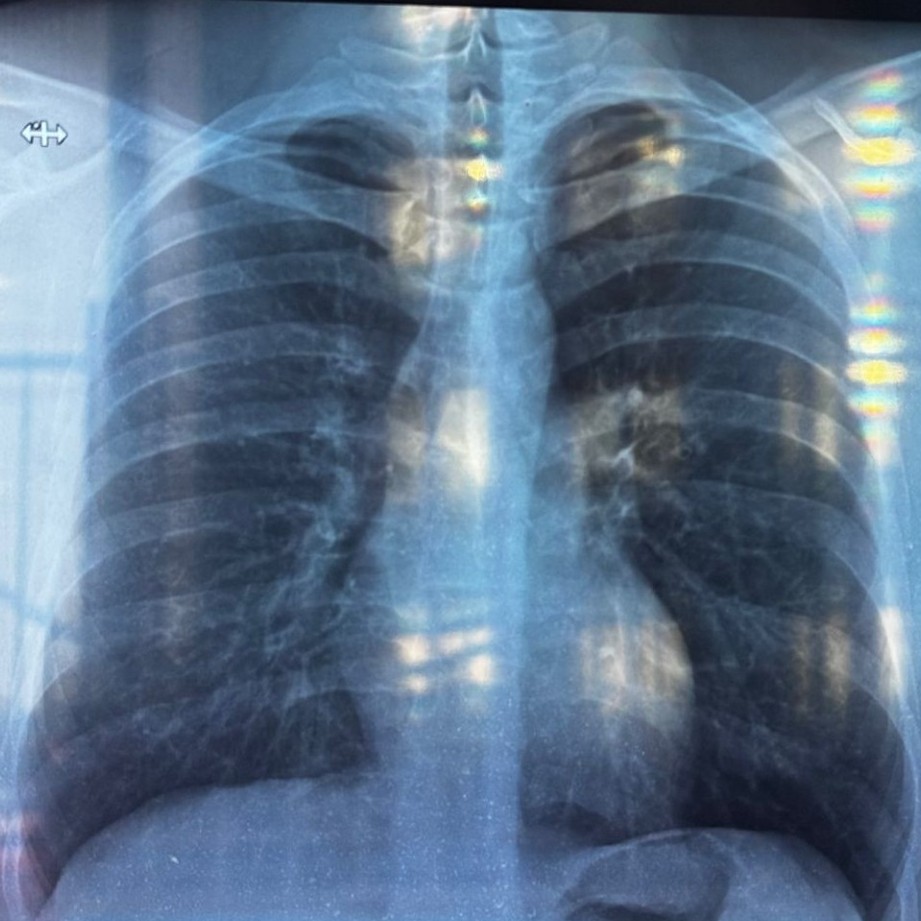

Однако, я могу описать некоторые общие наблюдения, которые видны на представленных рентгеновских снимках грудной клетки (прямая и боковая проекции):

На прямом снимке:

* Легочные поля выглядят относительно прозрачными.

* Легочный рисунок прослеживается, возможно, несколько усилен в прикорневых областях, что может быть вариантом нормы или указывать на некоторые изменения.

* Контуры диафрагмы четкие.

* Сердце имеет нормальные размеры и форму.

* Костные структуры (ребра, ключицы) без видимых грубых патологических изменений.

* В области верхушек легких и прикорневых зонах могут быть видны некоторые уплотнения или изменения, которые требуют более детальной оценки специалистом.